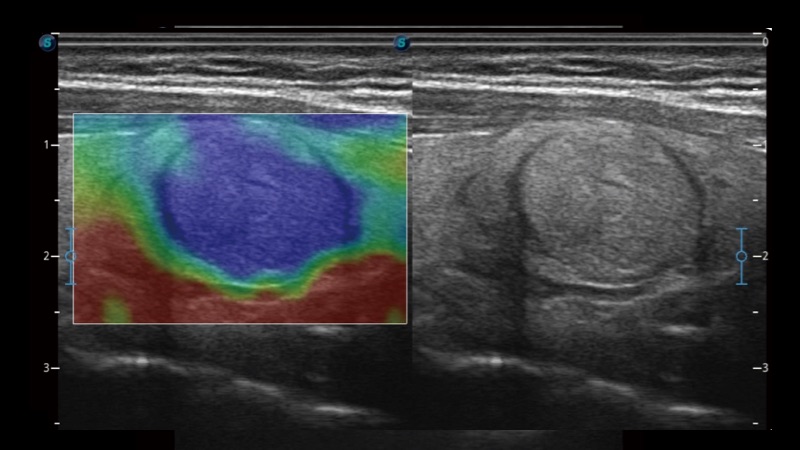

開立醫(yī)療通過不斷的技術(shù)創(chuàng)新,為大眾的生命健康提供持續(xù)關(guān)愛。P12 Plus采用全新一代超聲成像平臺,新平臺旨在將真實(shí)還原組織解剖結(jié)構(gòu)作為首要目標(biāo)。平臺采用全新集成化硬件模塊,搭載新一代芯片,系統(tǒng)性能得到大幅提升,為您的診斷提供了豐富的臨床信息。優(yōu)異的圖像表現(xiàn),豐富的探頭配置,全面的應(yīng)用功能,為您日常診斷提供了可靠的助手。

P12 Plus

彩色多普勒超聲診斷系統(tǒng)